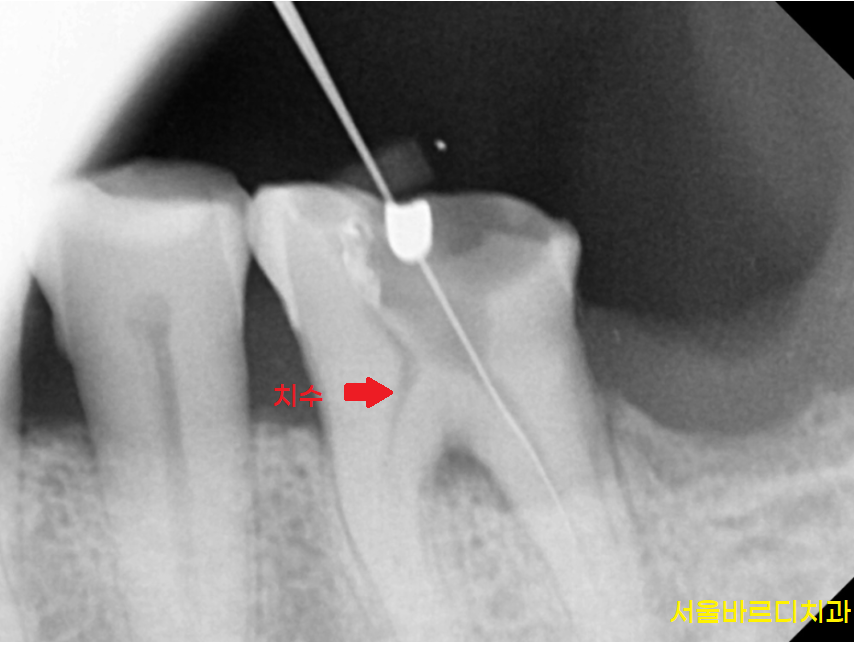

초기 치수염 증상일 수 있습니다.

치아 내부 신경에 문제가 생겼을 수 있어요!!

치아 신경에 문제가 생기는 치수염의 대표적인 증상이

뜨거운 음식을 먹었을 때 욱신거리는 통증이거든요~

치수염은 치아 내부에 위치한 신경과 혈관 조직에

염증이 생긴 상태를 말합니다.

뜨거운 물 시큰거리면 대부분 신경치료를 통해

치수 내부 염증을 치료하면 좋아집니다.